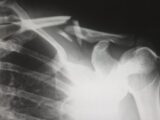

最終的に、彼女の首のスキャン画像を撮影したことで驚くべき事実が判明する。あくびの勢いで、彼女の首の第6頸椎と第7頸椎が前方に「飛び出し」、脊髄に突き刺さっていたのである。

「クレイジーでした。あくびの力でC6とC7が脊椎に突き刺さったのです。医師は、こんなことはあまりに異常な事故だと言っていました」と、ヘイリーさんはTikTokで当時を振り返る。「母は、医師から『彼女が再び歩けるか、そして生き延びられるかは、五分五分です』と告げられたそうです」。